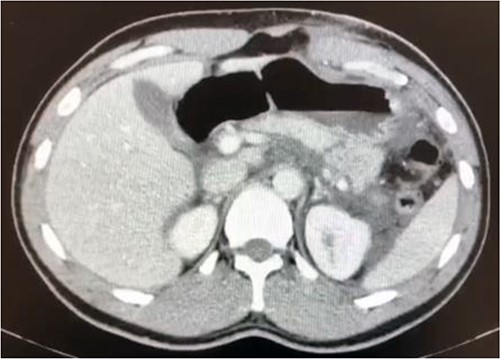

As shown in Fig. 1, an abdominal CT (computerized tomography) scan indicated a full pancreatic parenchyma transection along the body-to-tail transition. There was also a significant amount of free peritoneal fluid.

Transection of the pancreatic parenchyma throughout the distal body area (suggesting ductal damage) with a significant fluid collection.